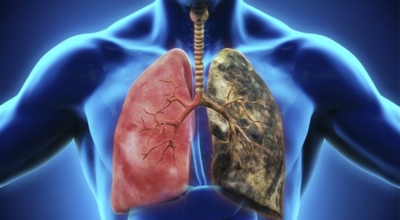

폐렴은 폐의 실질 조직에 염증이 생기는 질환으로, 주로 세균, 바이러스, 곰팡이 등의 감염에 의해 발생합니다. 폐렴은 감염성 질환이므로 전염될 수 있으며, 특히 면역력이 약한 영유아, 노인, 만성 질환자에게 더욱 위험합니다. 폐렴은 발생 위치에 따라 대엽성 폐렴과 기관지 폐렴으로 나뉘며, 원인균에 따라 세균성 폐렴, 바이러스성 폐렴, 곰팡이성 폐렴 등으로 분류됩니다.

- 흡연: 흡연은 폐 기능을 저하시키고 면역력을 떨어뜨려 폐렴 발병 위험을 높입니다.